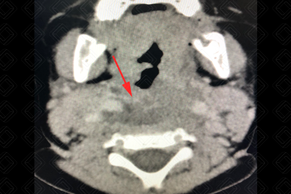

Texto alternativo para a imagem Figura 1. Créditos: Dra. Elazir Mota - Rio de Janeiro/RJ

Descrição das figuras 1 e 2: Evidenciando área hipodensa, sem realce pelo meio de contraste, mal definida, no espaço retrofaríngeo (setas vermelhas).

• Tomografia computadorizada do pescoço: Deve ser realizada, idealmente, com o uso do contraste venoso para identificar melhor a presença de coleções (figuras acima);